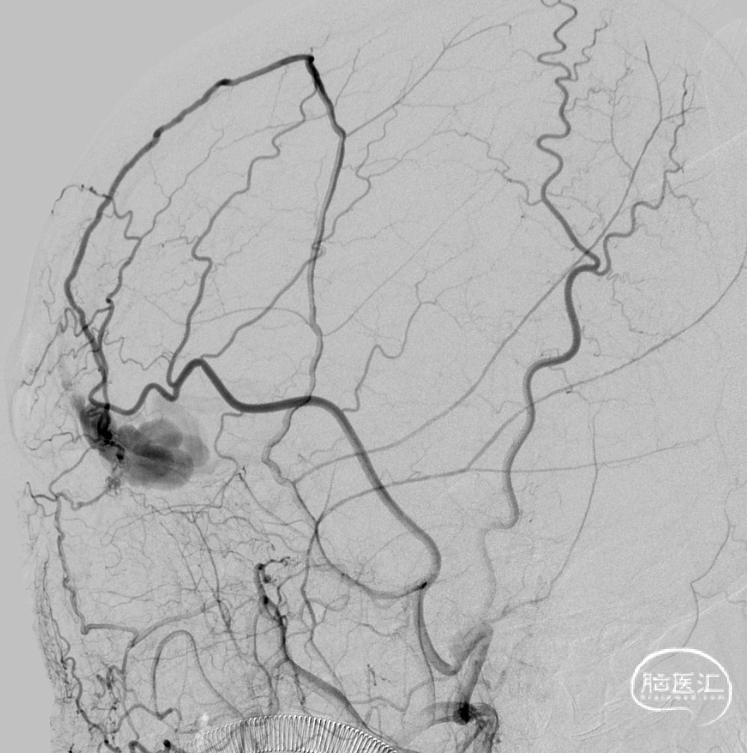

治疗经过

二期治疗